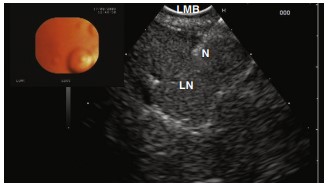

Endoscopic ultrasonography (EUS) and EBUS-TBNA have emerged as the techniques of choice for mediastinal nodal sampling in non–small cell lung cancer staging. Their precise diagnostic capabilities allow for accurate staging and assessment, significantly impacting treatment planning and prognosis.

The integration of EUS and EBUS provides a comprehensive view of the mediastinal nodes, surpassing the diagnostic accuracy of either technique used individually. This combined approach enhances nodal staging, crucial for determining the appropriate treatment path for NSCLC patients.

EUS Performed with the EBUS Scope